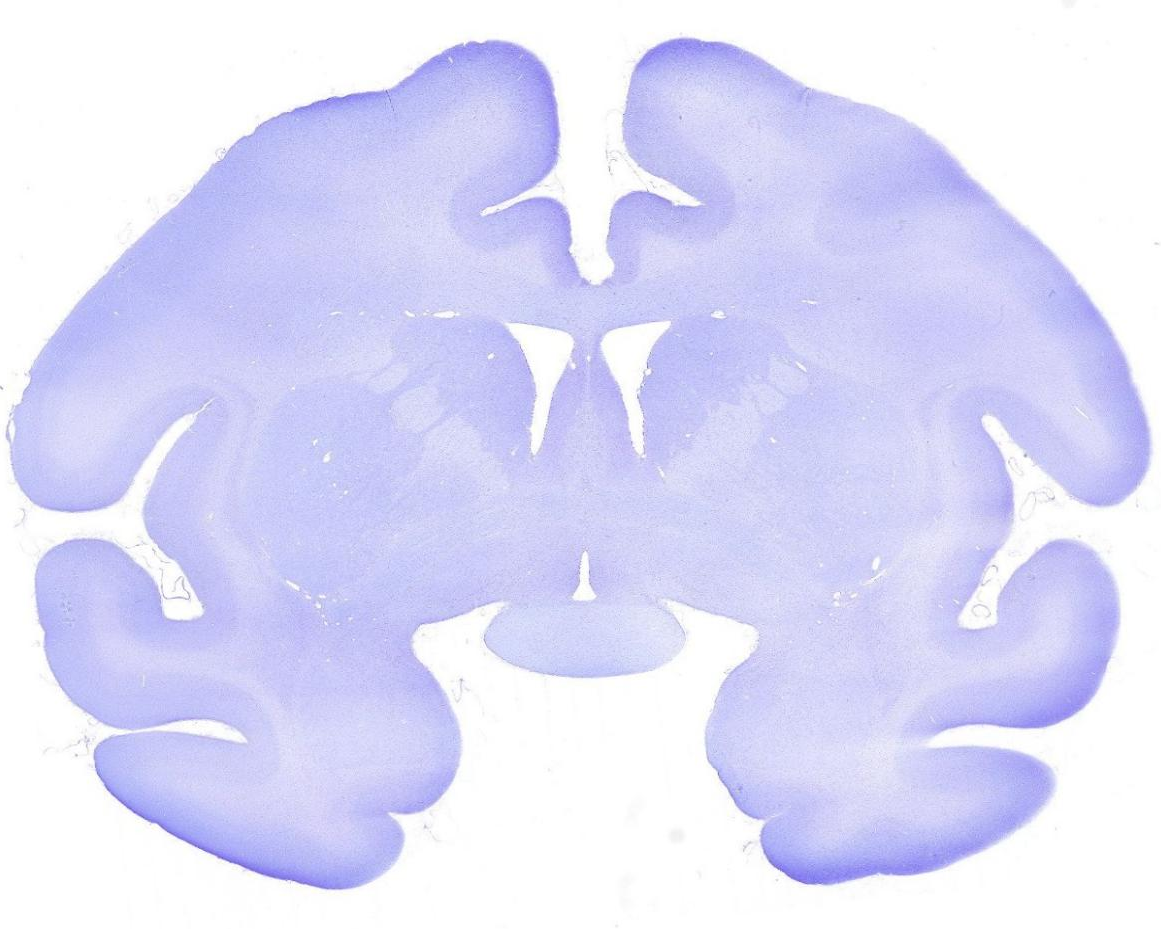

龙迈达斯食蟹猴整脑组织连续切片

猴脑切片是神经科学研究的重要手段,其核心目的可分为:揭示神经疾病机制、评估实验干预效果、推动技术开发与转化。然而相较于啮齿类动物脑组织,猴脑组织体积更大、结构更复杂、质地更软且不均匀,对其进行完整、精准且能良好保持形态的切片,是一项极

具挑战性的技术,往往需要经历一个持续的、精细化的摸索过程。

这一过程的核心在于不断优化:从前处理(如固定时间与渗透的均一性、脱水、包埋介质的选择以兼顾硬度与韧性),到切片设备与参数,每一个环节都可能显著影响切片效果。

对切片方位精度和厚度均匀性要求极高。包括针对后续尼氏染色过程中会出现的脱片情况,我们不断地改进实验条件和方法。

每一次尝试都是宝贵的经验积累,经过近一年这种反复的实践、观察、分析与改进,我公司最终顺利完成食蟹猴整脑连续切片约6000张,形成了猴脑整脑切片技术的操作流程,实现了国际少有的病理技术突破。

白片.png

石蜡切片

尼氏染色.png

尼氏染色